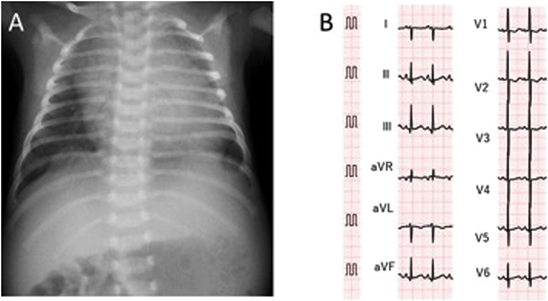

胸部レントゲンは心胸郭比69%と著明な心拡大および肺うっ血を認めた.12誘導心電図は正常洞調律,右軸偏位および右室肥大の所見を呈していた(Fig. 1).血液検査では,BNPが2544.8 pg/mLと著明な上昇を認めた(Table 1).RSウイルス検査は前医で陰性であった.

Fig. 1 Chest X-ray (A) and 12-lead electrocardiogram (B) on admission